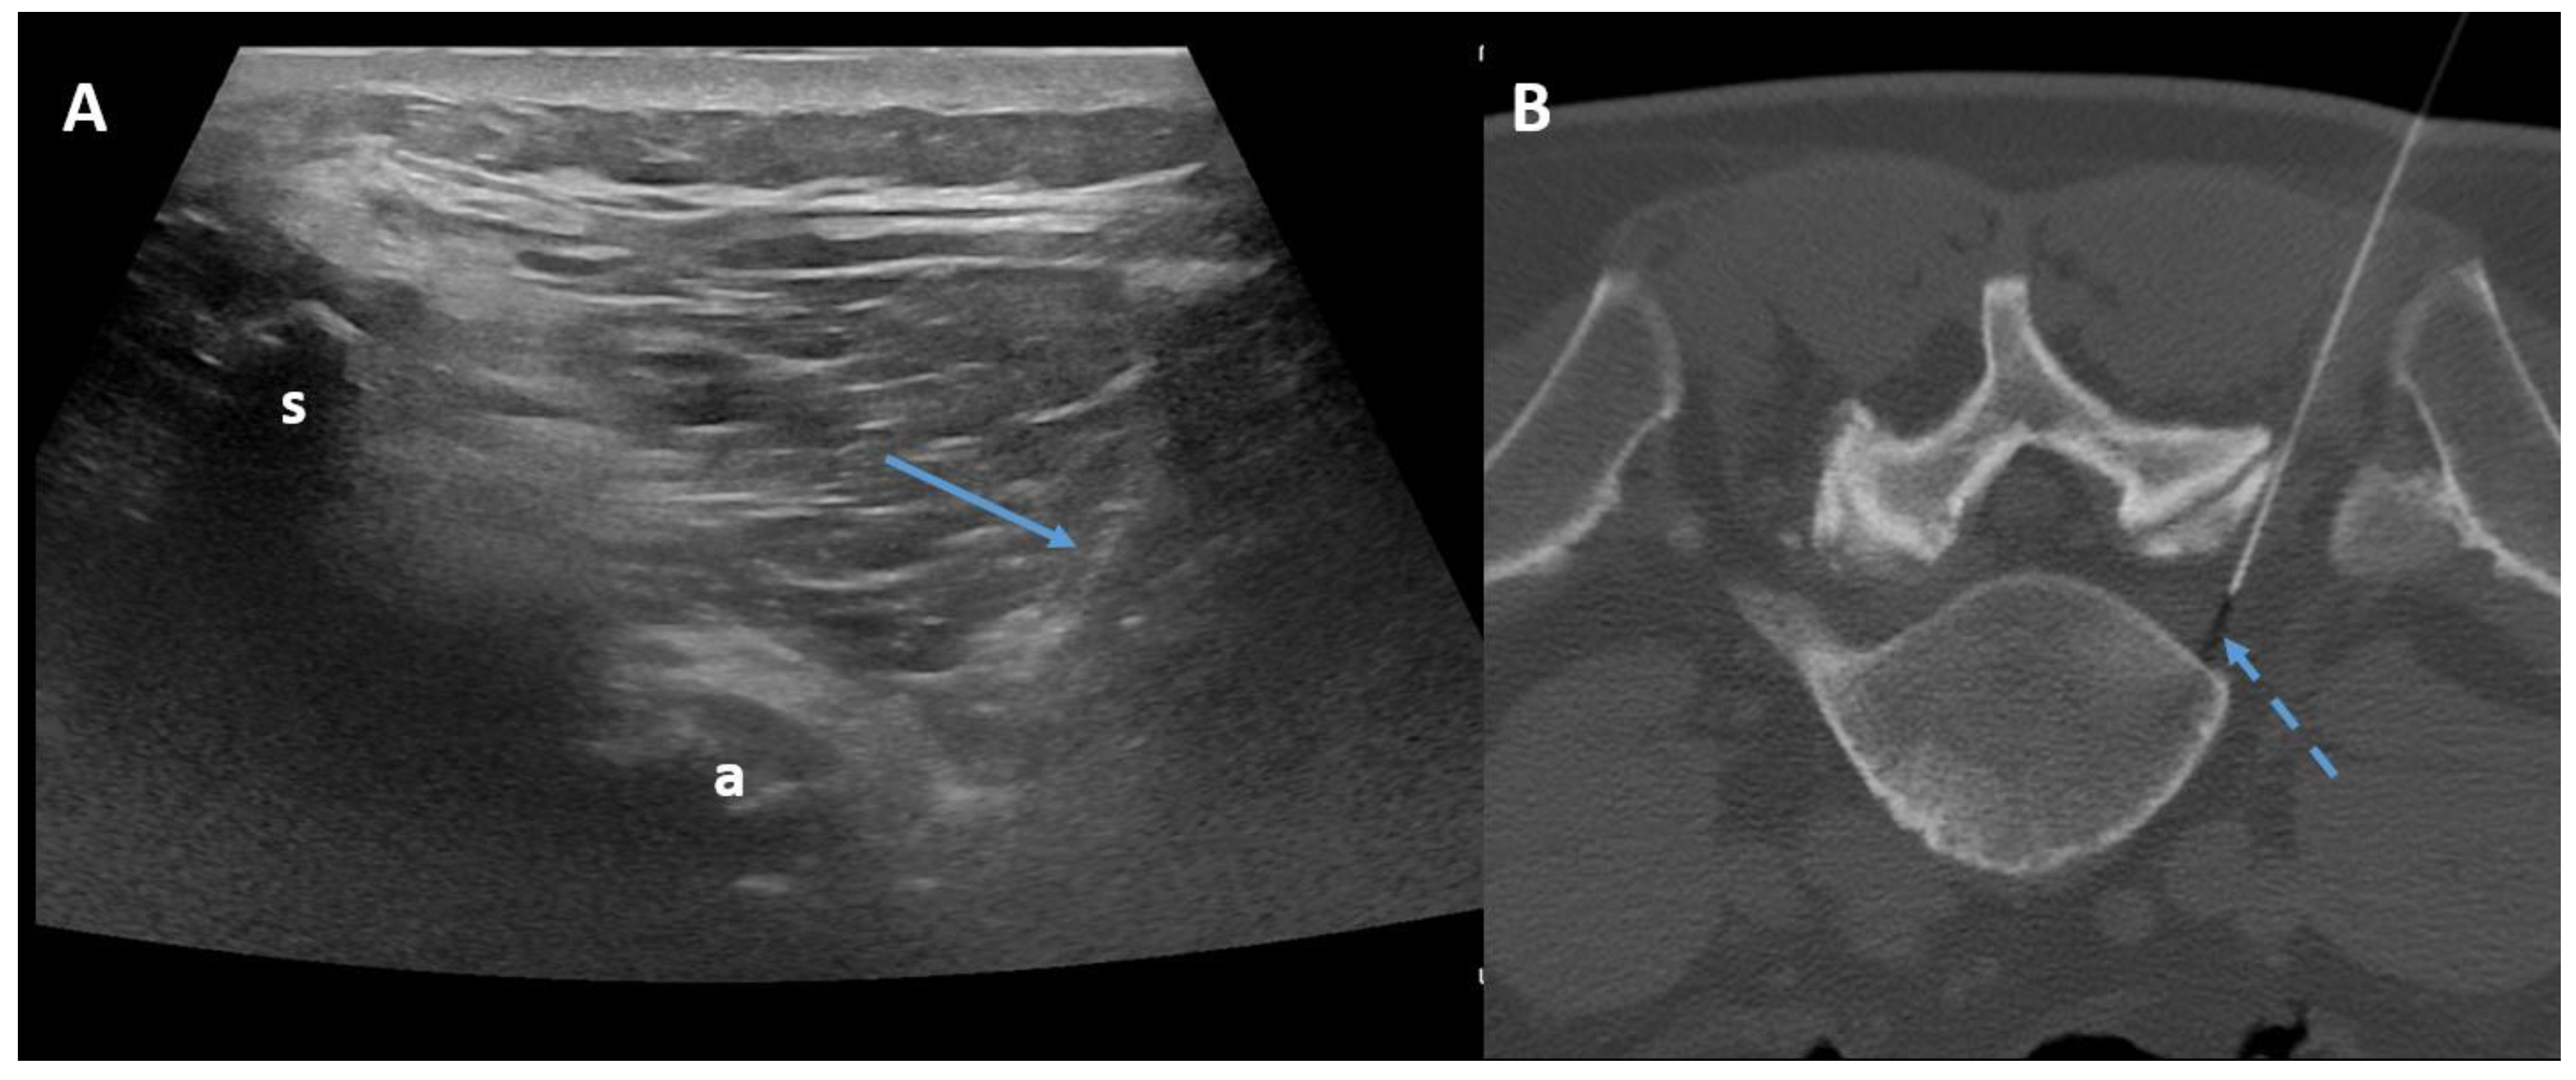

The transforaminal approach permits access to the compressed nerve roots that are a plausible origin of pain. The prone position with support under the abdomen or under the neck is sufficient both for the lumbar spine and for the cervical spine. Fluoroscopy, CT, or ultrasonography (US) may guide the needle, helping to maintain an inclination of 45° to 60°, laterally to the pedicles (Figure 4).

Figure 4.

Ultrasound-guided (Panel A) and CT-guided (Panel B) lumbar paraganglionic drug injection. Blue arrow = needle visualized on ultrasound. Dotted blue arrow = ganglion root. s = spinous process, a = posterior articular complex.

In fluoroscopy, the C-arm may be rotated to an angle of 45° along the same direction of the treated side, producing a superimposed virtual triangle, called the Scotty dog appearance, which guides the needle trajectory [59]. On CT, axial scans easily help to monitor the path from skin to foramen. The target is the foramen radicularis, and root contact is unnecessary. Radiopaque dyes can be used in order to confirm the needle placement if necessary. Therefore, once close to the nerve, medications may be injected, and the needle can be removed (Figure 5) [58,59].

Figure 5.

(A,B) Frontal and lateral view on fluoroscopic images of lumbar transforaminal injections with 22G needles.